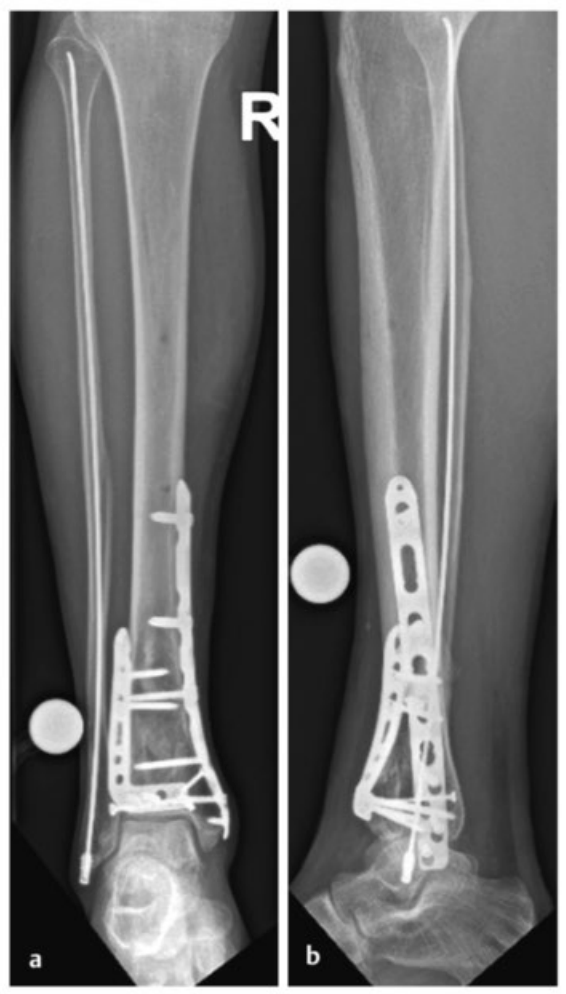

病例2受伤后入院首先植入跨踝关节外固定架,待软组织肿胀消退后,先对腓骨骨折进行微创固定,随后逐步完成复杂的胫骨Pilon骨折复位与固定。

术中临床图像显示了损伤的严重程度,同时体现了微创手术技术的优势,以及在必要时下胫腓联合切开复位重建的重要性。借助斯氏针的 “操纵杆(Joy-Stick)” 技术,可显著简化关节面的复位操作。

术后影像学随访检查显示骨折解剖复位,内植物位置良好。

患者术后恢复顺利,关节功能良好。术后12个月取出内植物,未发现创伤后关节炎征象。